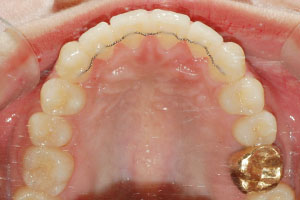

치료증례 전후사진

Before & After